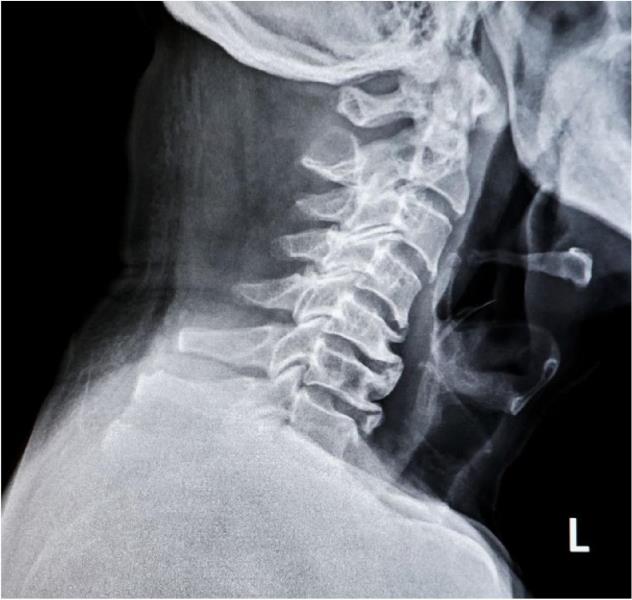

FORWARD HEAD POSTURE (FHP), ALSO DEscribed as cervical anterior translation, is one of the most common postural distortions seen in modern practice.

When the head sits forward of the thorax, joint mechanics change, cervical extensor demand rises, and afferent input from cervical mechanoreceptors is altered, influencing sensorimotor control.1 Clinically, chiropractors often observe FHP as part of broader kinetic-chain patterns that link cranial position with thoracic and pelvic alignment.2

Persistent anterior translation has been associated with neck pain, reduced cervical range of motion, and cervicogenic headache.3 Identifying the pattern and addressing contributing drivers can improve both short-term symptom relief and long-term postural resilience.

Cervical anterior translation refers to anterior displacement of the craniocervical complex relative to the thoracic cage. In a neutral standing posture, it is commonly observed when the external auditory meatus falls anterior to the acromioclavicular (AC) joint line.4

The pattern typically includes lower cervical flexion with compensatory upper cervical extension and may present with changes in the “bite line” and head-neck hinging.5 Classic clinical texts have long emphasized the mechanical cost of this position.

Cailliet19 20 noted that each inch of forward translation can substantially increase cervical muscular effort by approximately 10 pounds of tension. Curl20-21 described increased compressive loading in the lower cervical segments, particularly C5 to C7, due to a longer lever arm.

Common accompanying findings include rounded shoulders, increased thoracic kyphosis, humeral internal rotation, and soft-tissue thickening at the cervicothoracic junction.6 Recognizing FHP as a predictable cluster of compensations helps clinicians avoid treating the cervical spine in isolation and instead target the primary driver(s) of the pattern.